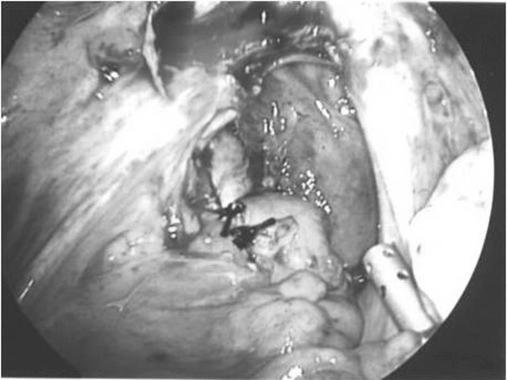

经腹腔镜从乙状结肠取出一枚铜宫内节育器。

Laparoscopic removal of a copper intrauterine device from the sigmoid colon.

IUD translocation to the sigmoid colon after uterine perforation is a rare but serious event. Removal of the IUD in such a situation has been recommended because of the risk of complication, such as fistula formation and colonic perforation. We present the case of a 43-year-old female with a copper T380A IUD embedded in the sigmoid colon, which was removed with minimally invasive techniques.

子宫穿孔后宫内节育器(IUD)移位至乙状结肠是一种罕见但严重的事件。由于存在诸如瘘管形成和结肠穿孔等并发症风险,建议在这种情况下取出IUD。我们报告一例43岁女性病例,其铜T380A宫内节育器嵌入乙状结肠,采用微创技术将其取出。